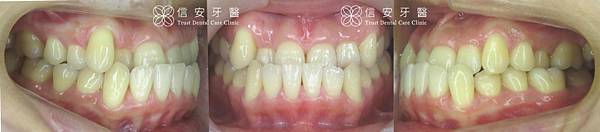

▲案例小靜主訴是第三級咬合不正、下顎反咬,下唇嚴重外翻,外型有嚴重戽斗。

▲上下顎的錯咬情形嚴重,影響外觀甚鉅。

▲小靜只花一年時間,就把原本異常的咬合關係矯正到正確位置上,現在講話再也不「漏風」了!

▲側面錯咬的情形也已經改善

▲小靜一顆牙都沒有拔!牙齒卻依舊排列的相當理想整齊